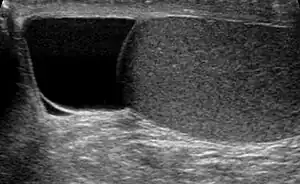

| Ultrasound of a testicle (grey) and a spermatocele (black). | |

| Diagnostic method | Examination, ultrasound[6] |

The primary care physician may diagnose and manage benign causes of scrotal masses such as hydrocele, varicocele and spermatocele. However, if a "must not miss" diagnoses related to testicular masses such as testicular torsion, epididymitis, acute orchitis, strangulated hernia and testicular cancer is suspected, the family physician must refer to a urologist.[16] Finding a painless, cystic mass at the head of the epididymis that is clearly separate from the testicle can indicate a spermatocele. Shining a light through the mass through a process known as transillumination can also help differentiate between a fluid-filled cyst and a tumor, which would not allow as much light to pass.[17] If uncertainty exists, ultrasonography of the scrotum can confirm the presence of a spermatocele.[14] The location and history of any scrotal masses are crucial in determining whether or not the mass is benign or malignant.[18] Lab tests such as a complete blood count (CBC test) or urine test can also be conducted to check for any possible infection or signs of inflammation.[19]

Upon physical examination, if a 'lump' is found during the testicular exam, further screening may be performed via ultrasound to eliminate testicular cancer.[8]